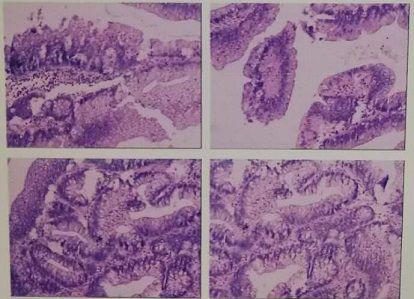

• 肠镜:结肠癌,结肠黑变病,痔疮(见图2),病理回报:结肠肝曲绒毛状腺瘤伴高级别上皮内瘤变(见图3)

图 3病理检查

病理回报:绒毛状腺瘤伴高级别上皮内瘤变,部分区域癌变为高分化腺癌,肿瘤侵深肌层,肠系膜肿大淋巴结3枚(见图4)。

图 4 病理检查